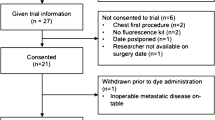

The study is a retrospective analysis of a prospectively maintained database carried out at the Department of Surgical Oncology at a tertiary cancer center in South India. Between October 2020 and till January 2023, 203 patients were operated at our institute. Among which 123 were operated by single surgical team, and 102 procedures were transthoracic esophagectomies (TTE). In the current study, 99 patients with resectable esophageal and gastroesophageal junctional (GEJ) cancer who underwent curative intent MAE were included. Patients aged between 18 and 75 years, who provided written informed consent, were eligible for the study. Patients allergic to iodine, those who did not undergo TTE, who did not consent, and those who were pregnant were excluded. The study was approved by the Medical Ethical Committee of the institute.